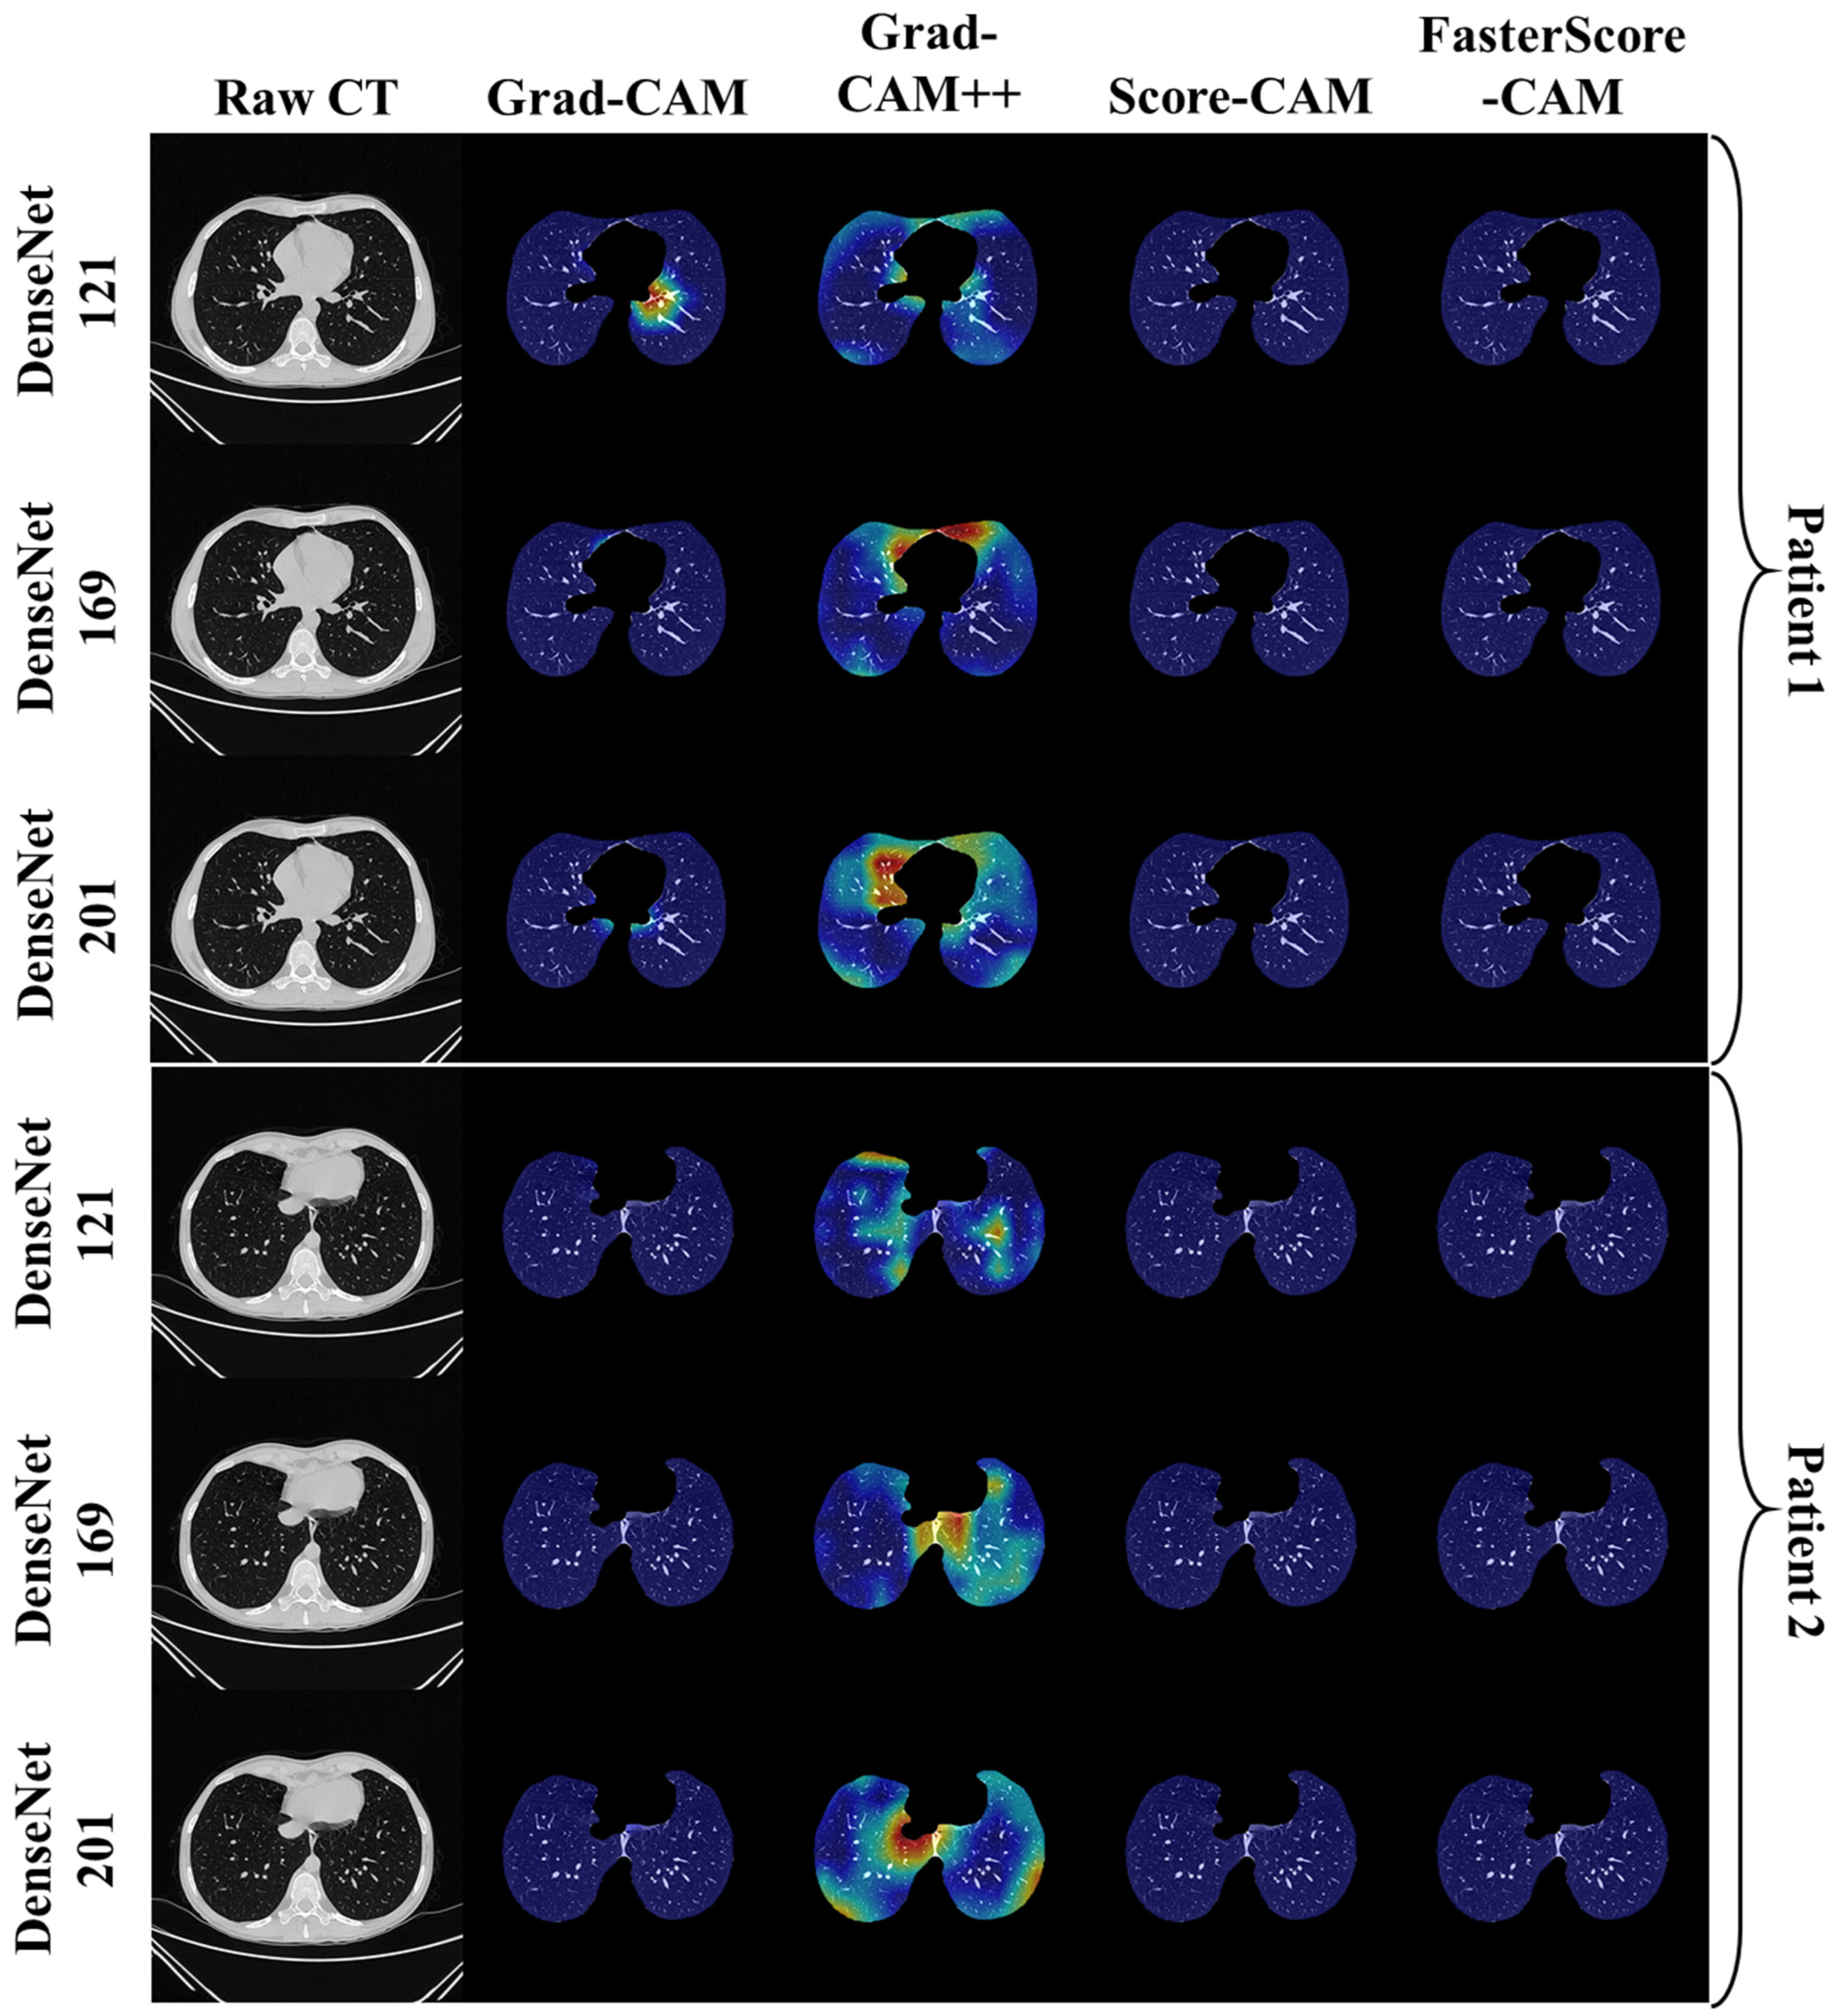

Visual Results Representing Lesion Using the Four CAM Techniques